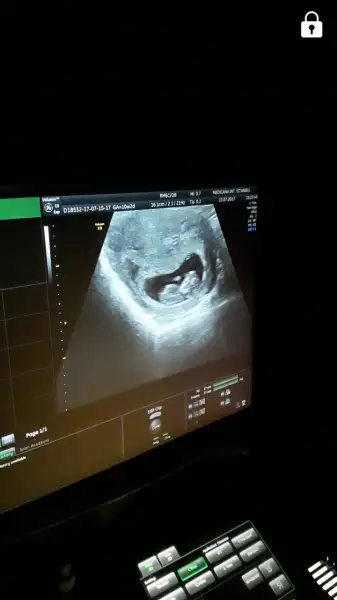

Maşallah Canım Bence bu bi erkeekkKızlar biz geldik herşey süper çıktı Allah'a şükür.. darısı sizlere bizimki elini ağzına götürüp duruyordu :)) cinsiyeti sordum şimdilik erken diye bişey demedi doktor tahminlerinizi alalım teyzeler sizce ne :)